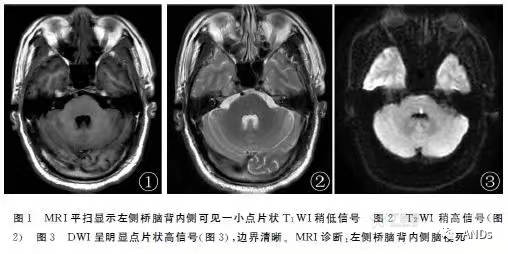

影像学表现: